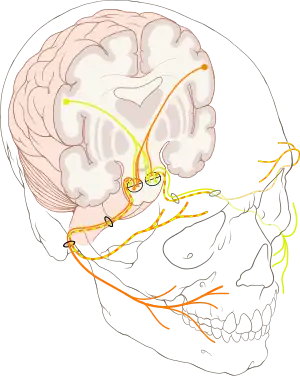

E. Nerves of the nose

The sensations registered by the human nose derive from the first two branches of cranial nerve V, the trigeminal nerve. The nerve listings indicate the respective innervation (sensory distribution) of the trigeminal nerve branches within the nose, the face, and the upper jaw (maxilla).

- The indicated nerve serves the named anatomic facial and nasal regions

Ophthalmic division innervation

- Lacrimal nerve – conveys sensation to the skin areas of the lateral orbital (eye socket) region, except for the lacrimal gland.

- Frontal nerve – conveys sensation to the skin areas of the forehead and the scalp.

- Supraorbital nerve – conveys sensation to the skin areas of the eyelids, the forehead, and the scalp.

- Supratrochlear nerve – conveys sensation to the medial region of the eyelid skin area, and the medial region of the forehead skin.

- Nasociliary nerve – conveys sensation to the skin area of the nose, and the mucous membrane of the anterior (front) nasal cavity.

- Anterior ethmoid nerve – conveys sensation in the anterior (front) half of the nasal cavity: (a) the internal areas of the ethmoid sinus and the frontal sinus; and (b) the external areas, from the nasal tip to the rhinion: the anterior tip of the terminal end of the nasal-bone suture.

- Posterior ethmoid nerve – serves the superior (upper) half of the nasal cavity, the sphenoids, and the ethmoids.

- Infratrochlear nerve – conveys sensation to the medial region of the eyelids, the palpebral conjunctiva, the nasion (nasolabial junction), and the bony dorsum.

The maxillary division innervation

- Maxillary nerve – conveys sensation to the upper jaw and the face.

- Infraorbital nerve – conveys sensation to the area from below the eye socket to the external nares (nostrils).

- Zygomatic nerve – through the zygomatic bone and the zygomatic arch, conveys sensation to the cheekbone areas.

- Superior posterior dental nerve – sensation in the teeth and the gums.

- Superior anterior dental nerve – mediates the sneeze reflex.

- Sphenopalatine nerve – divides into the lateral branch and the septal branch, and conveys sensation from the rear and the central regions of the nasal cavity.

The supply of parasympathetic nerves to the face and the upper jaw (maxilla) derives from the greater superficial petrosal (GSP) branch of cranial nerve VII, the facial nerve. The GSP nerve joins the deep petrosal nerve (of the sympathetic nervous system), derived from the carotid plexus, to form the vidian nerve (in the vidian canal) that traverses the pterygopalatine ganglion (an autonomic ganglion of the maxillary nerve), wherein only the parasympathetic nerves form synapses, which serve the lacrimal gland and the glands of the nose and of the palate, via the (upper jaw) maxillary division of cranial nerve V, the trigeminal nerve.